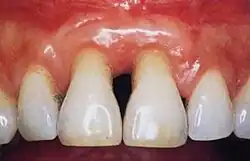

Normal gingiva may range in color from light coral pink to heavily pigmented. The soft tissues and connective fibres that cover and protect the underlying cementum, periodontal ligament and alveolar bone are known as the gingivae. The gingivae are categorized into three anatomical groups: the free, attached and the interdental gingiva. Each of the gingival groups are considered biologically different; however, they are all specifically designed to help protect against mechanical and bacterial destruction.[3]

Gingivitis is a common condition that affects the gingiva or mucosal tissues that surround the teeth. The condition is a form of periodontal disease; however, it is the least devastating, in that it does not involve irreversible damage or changes to the periodontium (gingiva, periodontal ligament, cementum or alveolar bone). It is commonly detected by patients when gingival bleeding occurs spontaneously during brushing or eating. It is also characterized by generalized inflammation, swelling, and redness of the mucosal tissues. Gingivitis is typically painless and is most commonly a result of plaque biofilm accumulation, in association with reduced or poor oral hygiene. Other factors may increase a person's risk of gingivitis, including but not limited to systemic conditions such as uncontrolled diabetes mellitus and some medications. The signs and symptoms of gingivitis can be reversed through improved oral hygiene measures and increased plaque disruption. If left untreated, gingivitis has the potential to progress to periodontitis and other related diseases that are more detrimental to periodontal and general health.[10]

Healthy gingiva can be described as stippled, pale or coral pink in Caucasian people, with various degrees of pigmentation in other races.[15] The gingival margin is located at the cemento-enamel junction without the presence of pathology. The gingival pocket between the tooth and the gingival should be no deeper than 1–3mm to be considered healthy. There is also the absence of bleeding on gentle probing.[11]